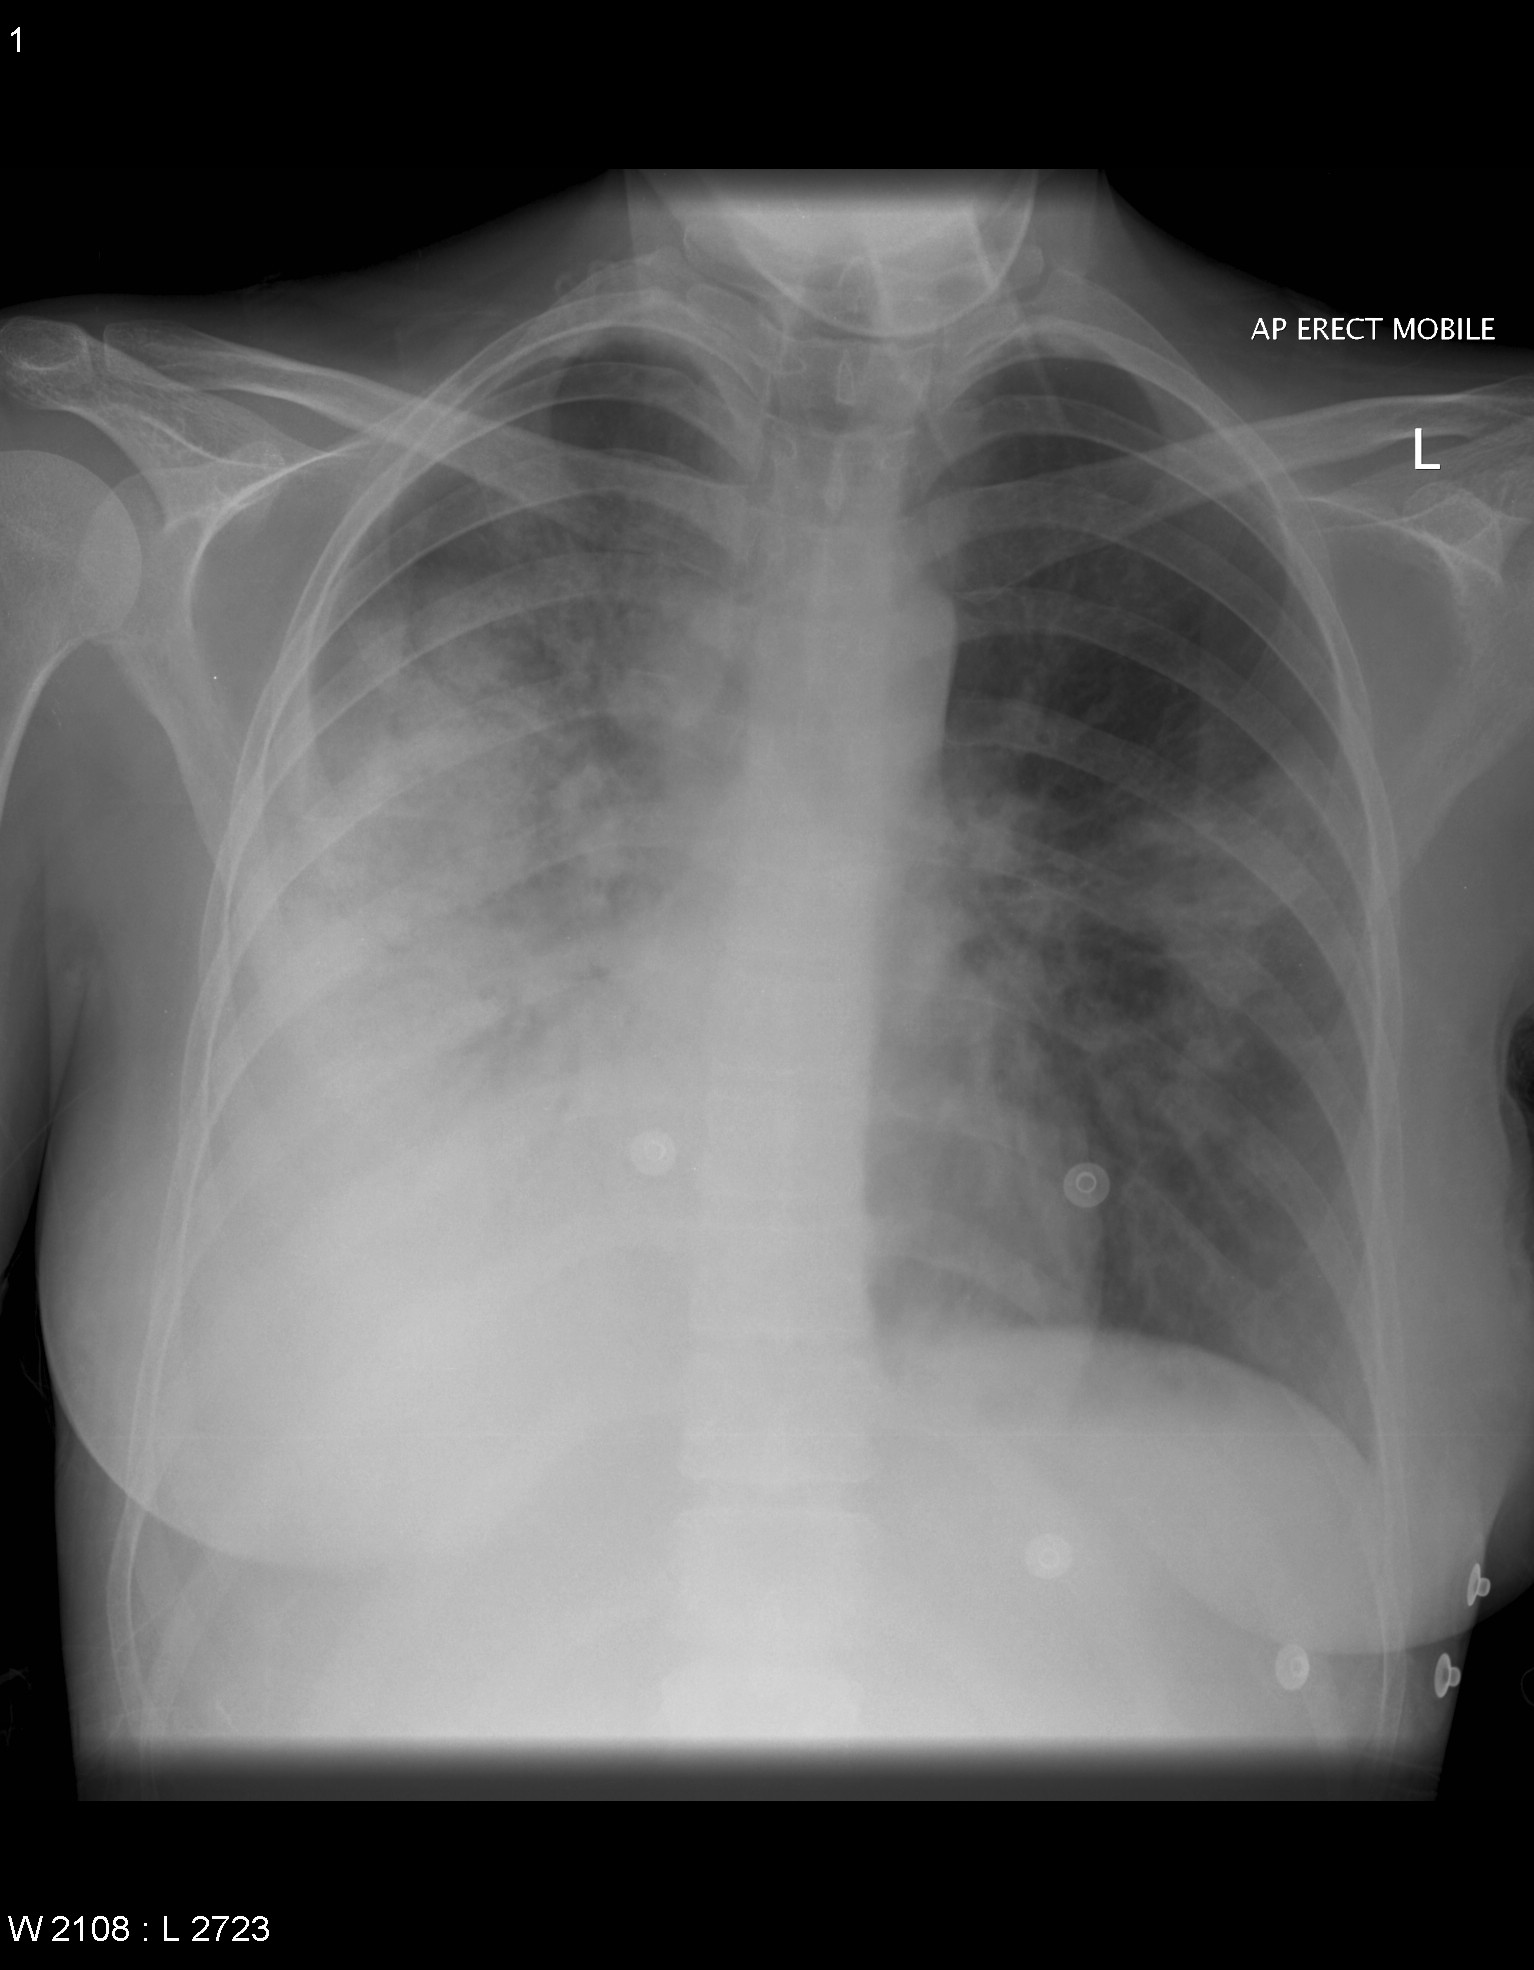

All our experiments use five-fold cross-validation to split target class. To compose the complete test set we use the fold used as a test, together with all the outliers samples. Finally, we repeat the approach twenty times taking means and variance to compare our results with other models. In our experiments we use six numerical datasets from UCI repository (see. Table. 5) and a novel dataset of Covid-19 that contains chest X-ray or CT images of positive/negative patients (see Fig. 1). In order to have the right comparison criterion in Covid-19 dataset, we extract confusion matrix as reported in Tab. 4 and compute the precision metric described in Eqs. 13 and 14. These last measures are needed to compare the class accuracy of the proposed OCdmst and the Resnet18 used in our experiments.

In the third experiment, we demonstrate by experimental results the effectiveness of our model with few data and compare it with a neural network (Resnet18). We simulate the scenario in which we have too few data to deny common neural networks to make right discrimination of different concepts (two classes in our case). Therefore we apply a 2-Fold cross-validation considering all data available from Covid-19 dataset and we extract the deep features for each model trained (Resnet18). All images have been re-scaled to 256x256 pixels and transformed to gray-scale. Learning rate and batch-size are set to 0.001 and 10 respectively. As evaluation metric we do not consider the total accuracy but we evaluate the accuracy for each class (Precision). Then, we use the deep features as input to our OCdmst using the dataset split in the previous step. The results reported in Tab. 2 show the flexibility of our model to operate also with

Resnet18 learned features using cross-entropy loss. As showed in Tab. 2, Resnet18 does not offer right prediction to recognize instances from negative class. This results is reasonable considering we have too few data with negative labels. Even when we used features extracted by Resnet18 to our model, but OCdmst is able to recognize value from both classes and overcome the right prediction also on positive class. The confusion matrix showed in Fig. 7 and accuracies for each class demonstrate the capability of OCdmst to operate also in a scenario with few data, as well as overcome deep neural networks. This last result is plausible because it represents one of the weaknesses of deep models.